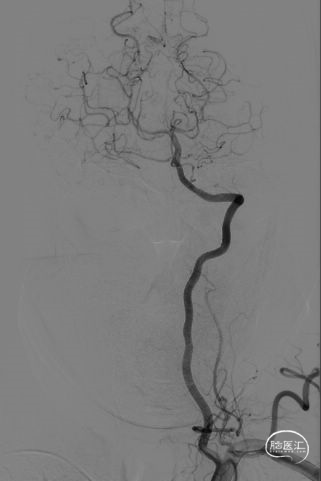

DSA左椎正位

DSA左椎侧位

右侧大脑中动脉M1段次全闭塞,见一“搭桥”动脉形成,远端血管显影尚可;右侧椎动脉V3段走形迂曲,V4段重度狭窄(约95%)。